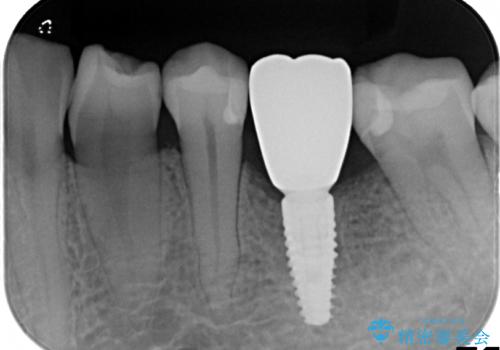

- 治療計画

- 保存不可能な歯の抜歯後、待時にてインプラントを埋入、2回法にて咬合回復を計画した。

インプラントの種類:strauman SLActive

かぶせ物の種類:Bellezza screw retain